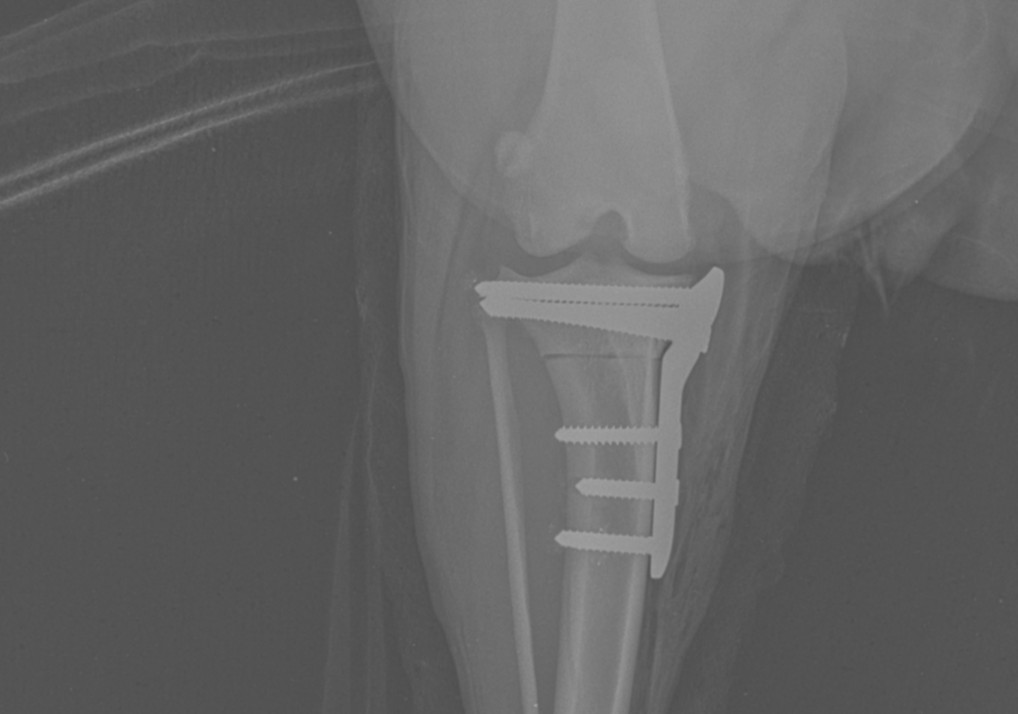

Die TPLO (tibia plateau leveling osteotomy) ist eine chirurgische Anpassung der Gelenkfläche des Schienbeinknochens nach einem Riss des vorderen Kreuzbandes.

Nach Diagnosestellung werden vor der Operation, Röntgenbilder des Kniegelenks, angefertigt. Es bedarf einer genauen OP-Planung um die richtige Platte, den korrekten Winkel und die passenden Schrauben für den Patienten zu finden.